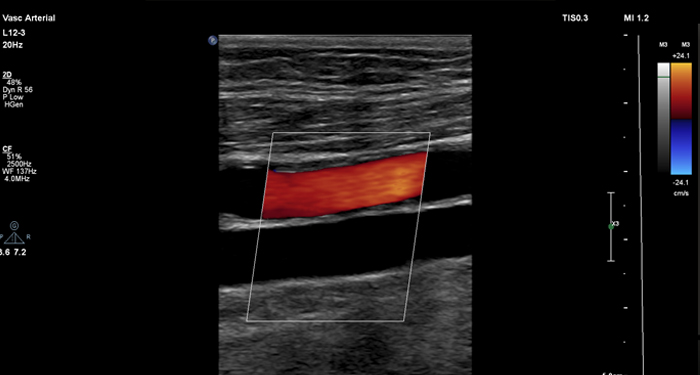

At the touch of a button, the new MaxVue high-definition display brings extraordinary visualisation of anatomy with 1,179,648 additional image pixels compared to a standard 4:3 display format mode. MaxVue enhances ultrasound viewing during interventional procedures and provides 38% more viewing area to optimise the display of dual, side/side, biplane, and scrolling imaging modes.

MaxVue offers a 38% greater viewing area.